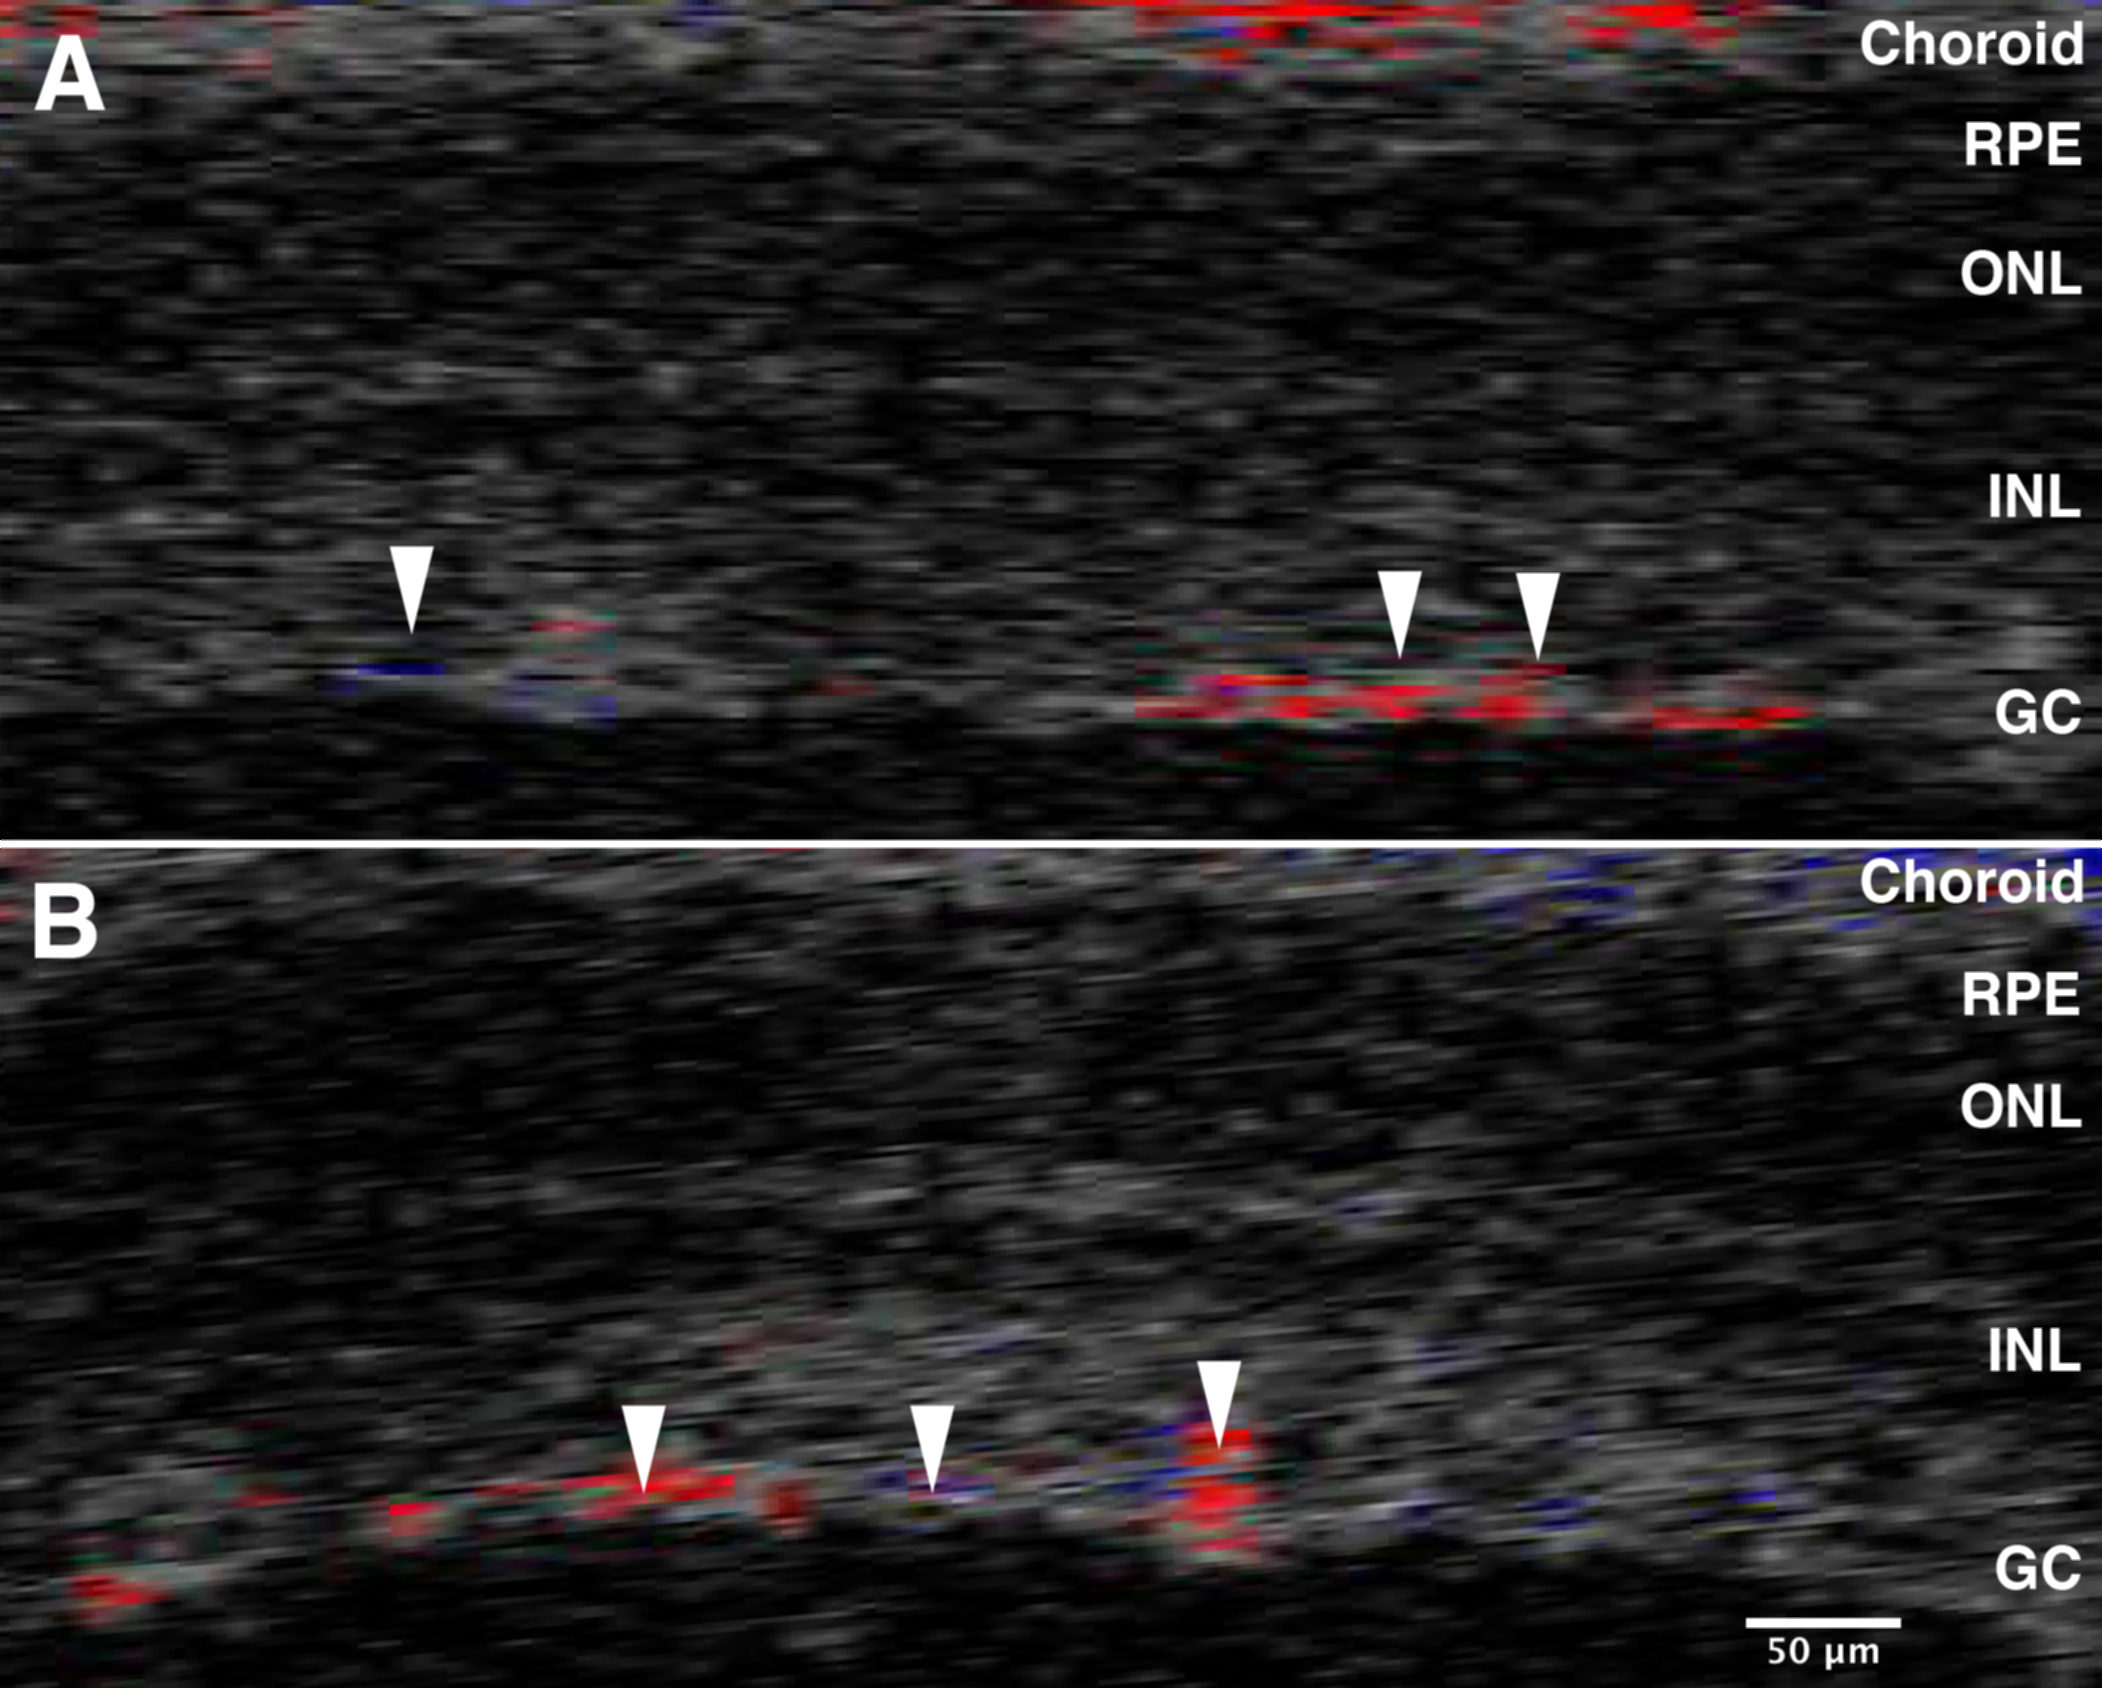

Figure 2. Optical coherence

tomography Doppler imaging before and after optic nerve crush

(ONC). OCT was used to measure blood flow using Doppler imaging.

We were able to confirm that there is continued perfusion of the

retina before and after ONC. Panel A shows the OCT

Doppler image of the retina immediately before ONC, and panel B

illustrates the blood flow immediately after ONC. The arrows

point to some of the vessels present on the surface of the

retina. The colors reflect the direction of blood flow; red is

flow toward the transducer and blue is flow away from the

transducer. These data demonstrate that in the mouse this

procedure does not interrupt blood flow to the retina. The

abbreviations in the figures are defined as follows: retinal

pigment epithelium (RPE), outer nuclear layer (ONL), inner

nuclear layer (INL), and ganglion cells (GC).